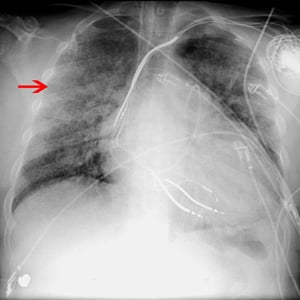

RX di un paziente con sindrome da distress respiratorio acuto

La freccia indica alcune delle opacità alveolari diffuse in un paziente con sindrome da distress respiratorio acuto.

© 2017 Elliot K. Fishman, MD.